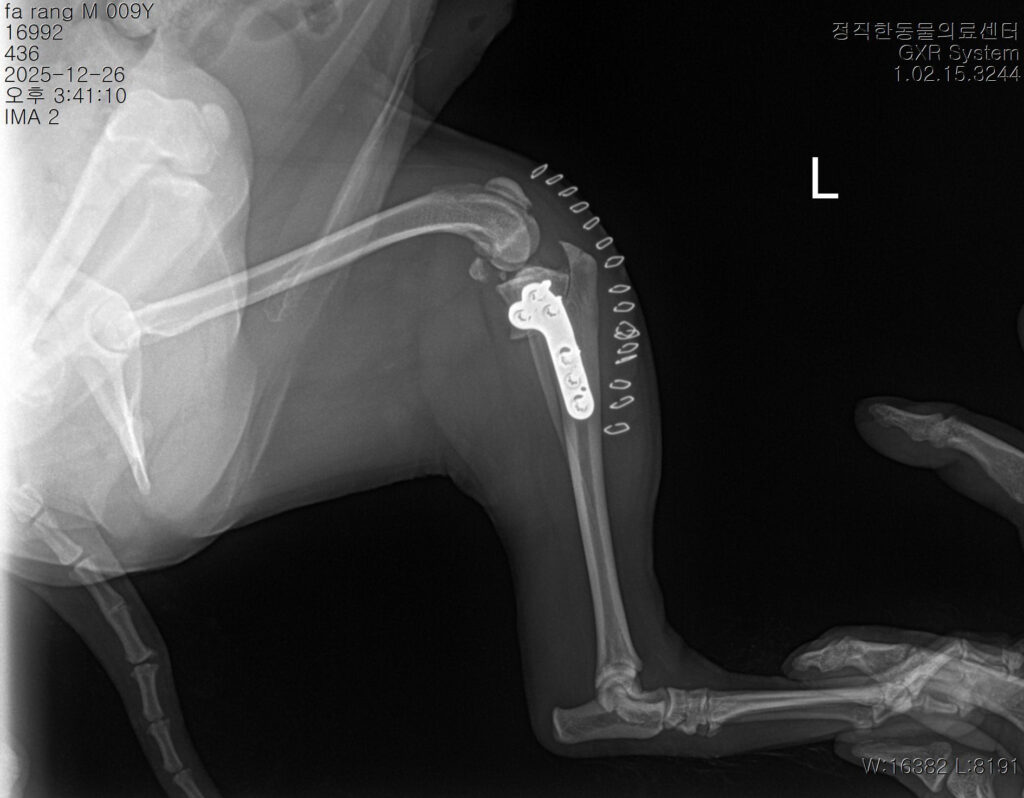

수술 전

(Before)

수술 후

(Afrer)